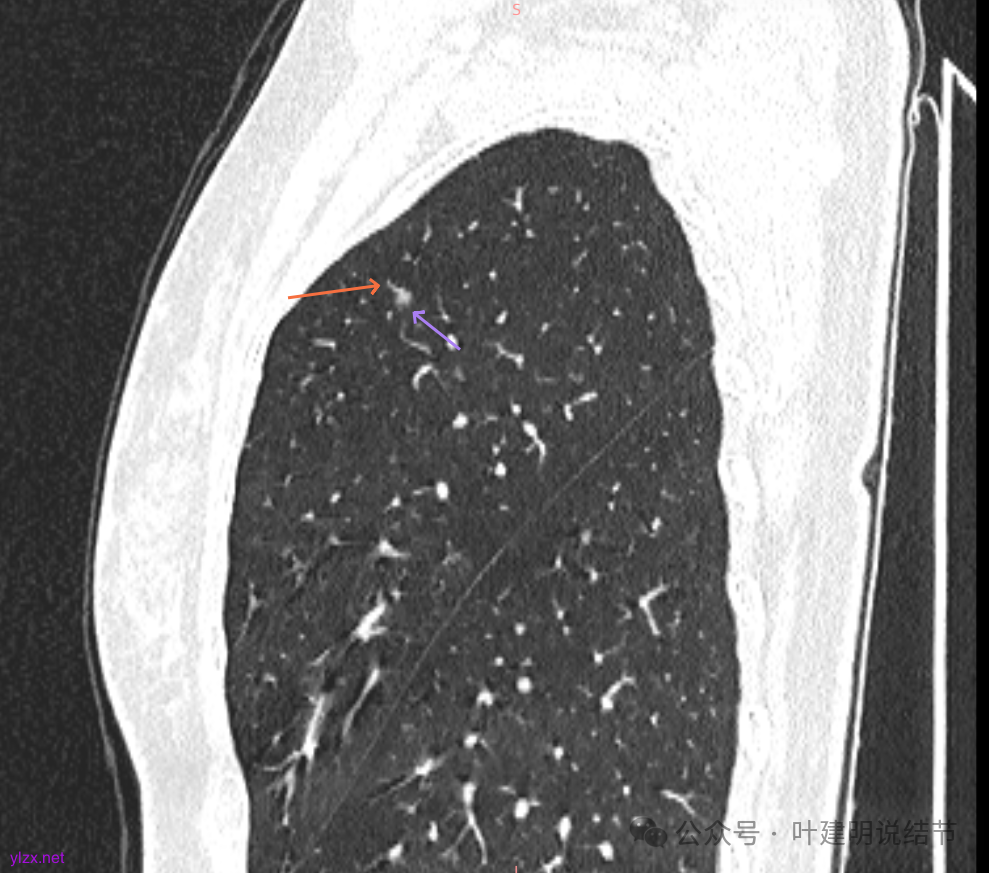

主病灶矢状位有血管进入,边缘毛糙,密度不纯,倒是更像肿瘤些。

再看2020年5月时的主病灶以及两次对比的影像:

两肺多发磨玻璃结节,我们主要看最主要的病灶有没有风险或者有没有进展就可以。我是先看2025年的,黄色的微小磨玻璃结节,密度很低,但是轮廓较为清楚,需要考虑肺泡上皮增生或者肺泡间隔增宽,严格意义上应该没有算肺癌,但是以后有可能会发展到不典型增生或者原位癌,当然也可能永远发展不到那个程度,所以目前不需要管;蓝色的到底是肺泡上皮增生还是少许慢性炎不太好确定,因为轮廓稍显模糊,但它又是磨玻璃密度,总归近期是能够随访的;橘色的密度比黄色的略高,有可能会使肺泡上皮增生或者不典型增生,目前也仍可以随访;粉色的是主病灶,位于左肺上叶,混合密度,表面毛糙,由小血管进入,单次看需要考虑微浸润性腺癌可能性较大。然后我们再来看2020年的影像,因为除了粉色的其他的都没有风险,所以不需要一一去找出来,重点关注粉色这处当时是怎样的。我们发现这个病灶5年前就有,也有小血管进入,也有表面毛糙,也是磨玻璃密度,但是当时磨玻璃当中没有实性的成分,是纯磨玻璃伴微小血管进入。对比起来看,这个病灶在5年当中略有进展,原来应该是腺体前驱病变,现在应该是原位癌或者微浸润性腺癌。那么是不是现在就到了一定得马上手术的程度呢?这个仍然可能是不同医生意见会有出入的。假如说从再随访是不是马上会转移来讲,这么小的肿瘤,发展这么慢,而且仍然含有磨玻璃成分,病理考虑与微浸润性腺癌可能性较大,应该仍然不至于说没有随访的空间。但是如果继续随反思想压力比较大,以及即便在随访后续仍然总得要开刀来说,加上病灶位置靠胸膜并不远,简单的单孔胸腔镜楔形切除就能解决问题,将有一定风险的这个病灶切了,同样是可行的。这需要你自己权衡决定。我没有办法100%给十分确切的意见。但是如果从倾向性来讲,由于是多发病灶,加上年纪还轻,风险还不是很大,稍微清一下雨6~9个月复查,有进展病风险再增加再考虑手术。意见供你参考!